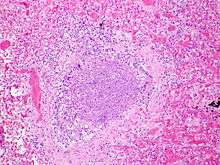

The term usually refers to acute viral bronchiolitis, a common disease in infancy. This is most commonly caused by respiratory syncytial virus[11] (RSV, also known as human pneumovirus). Other viruses which may cause this illness include metapneumovirus, influenza, parainfluenza, coronavirus, adenovirus, and rhinovirus.